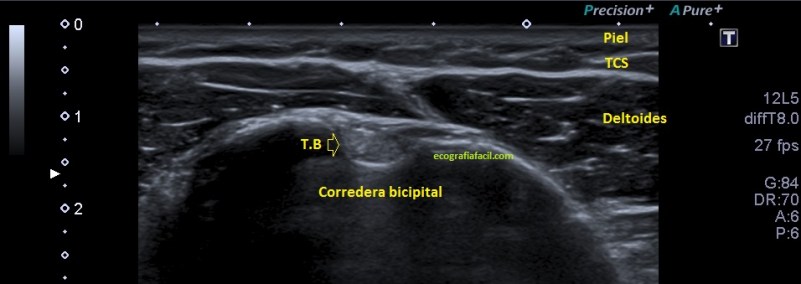

Si tu lo quieres estudiar en un corte transverso o eje corto del tendón verás como muestra de normalidad la imagen número 1. Semiológicamente es muy agradecido. Ves el tendón ovalado, hiperecogénico reposado en la corredera bicipital. El ligamento transverso humeral, hiperecogénico y lineal, anterior a la estructura tendinosa que descansa en la corredera.